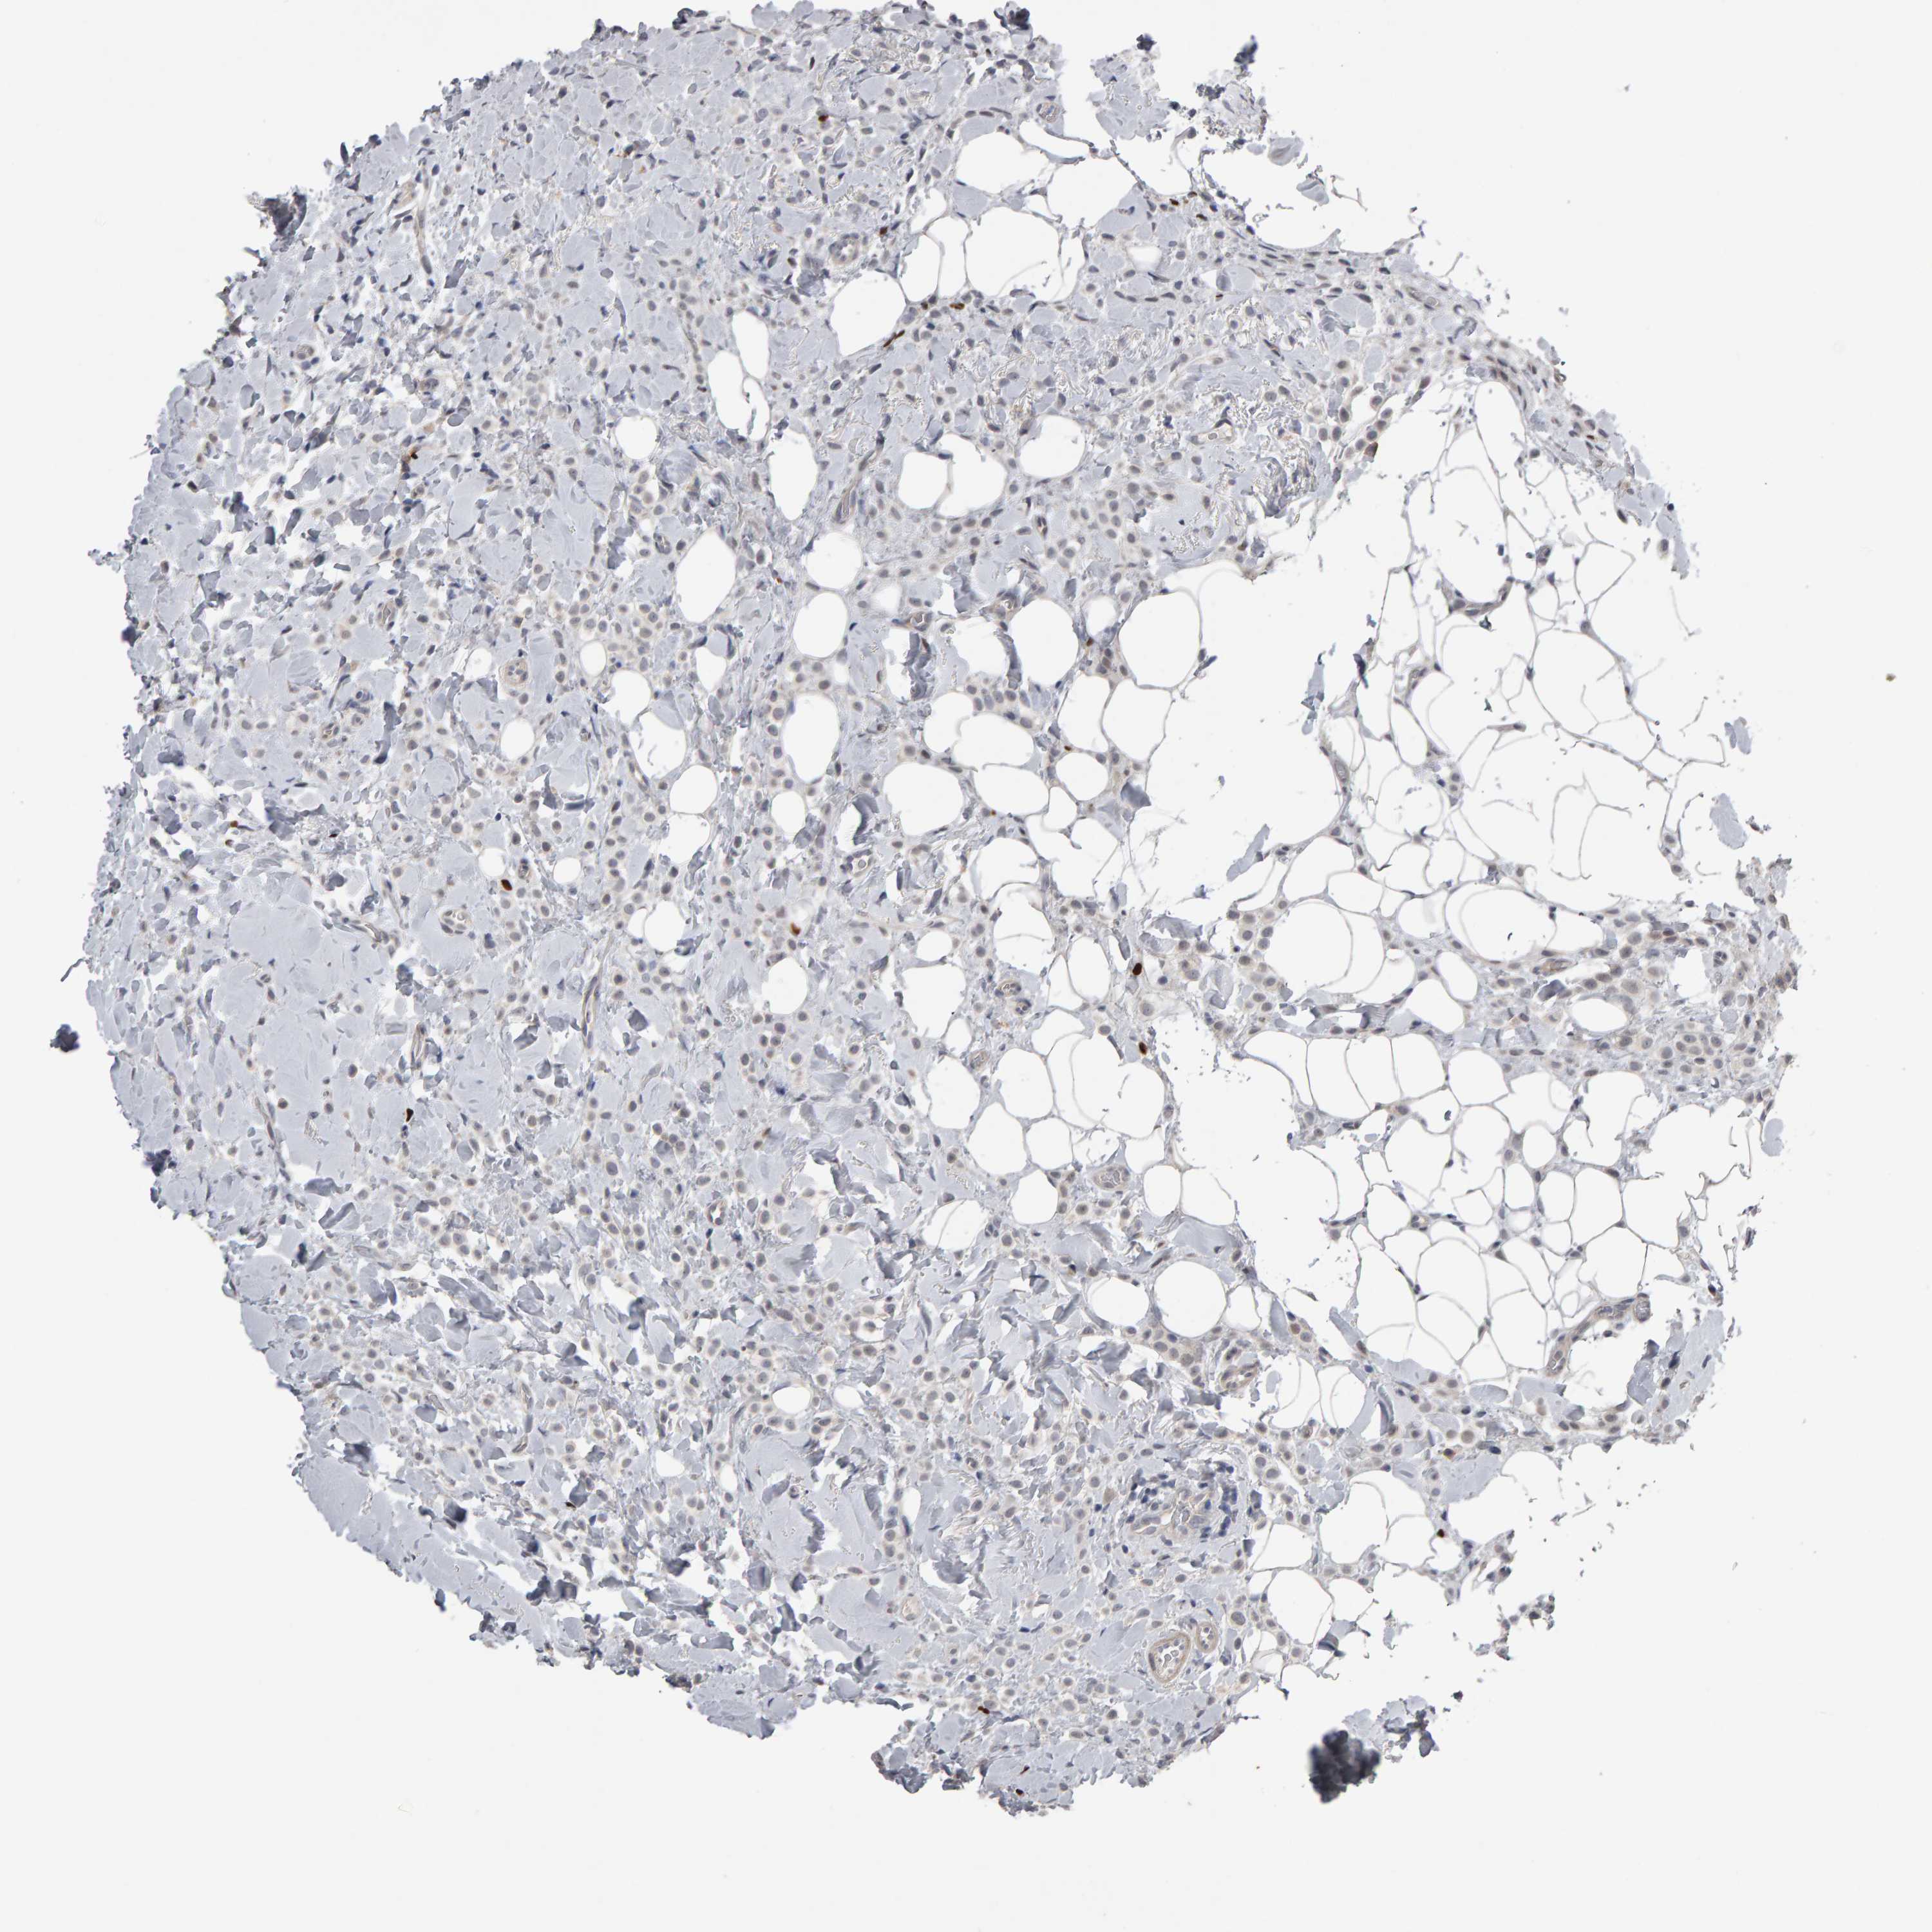

CANCER BREAST CANCER Show tissue menu

BRCA TCGA BRCA VALIDATION PROTEIN EXPRESSION